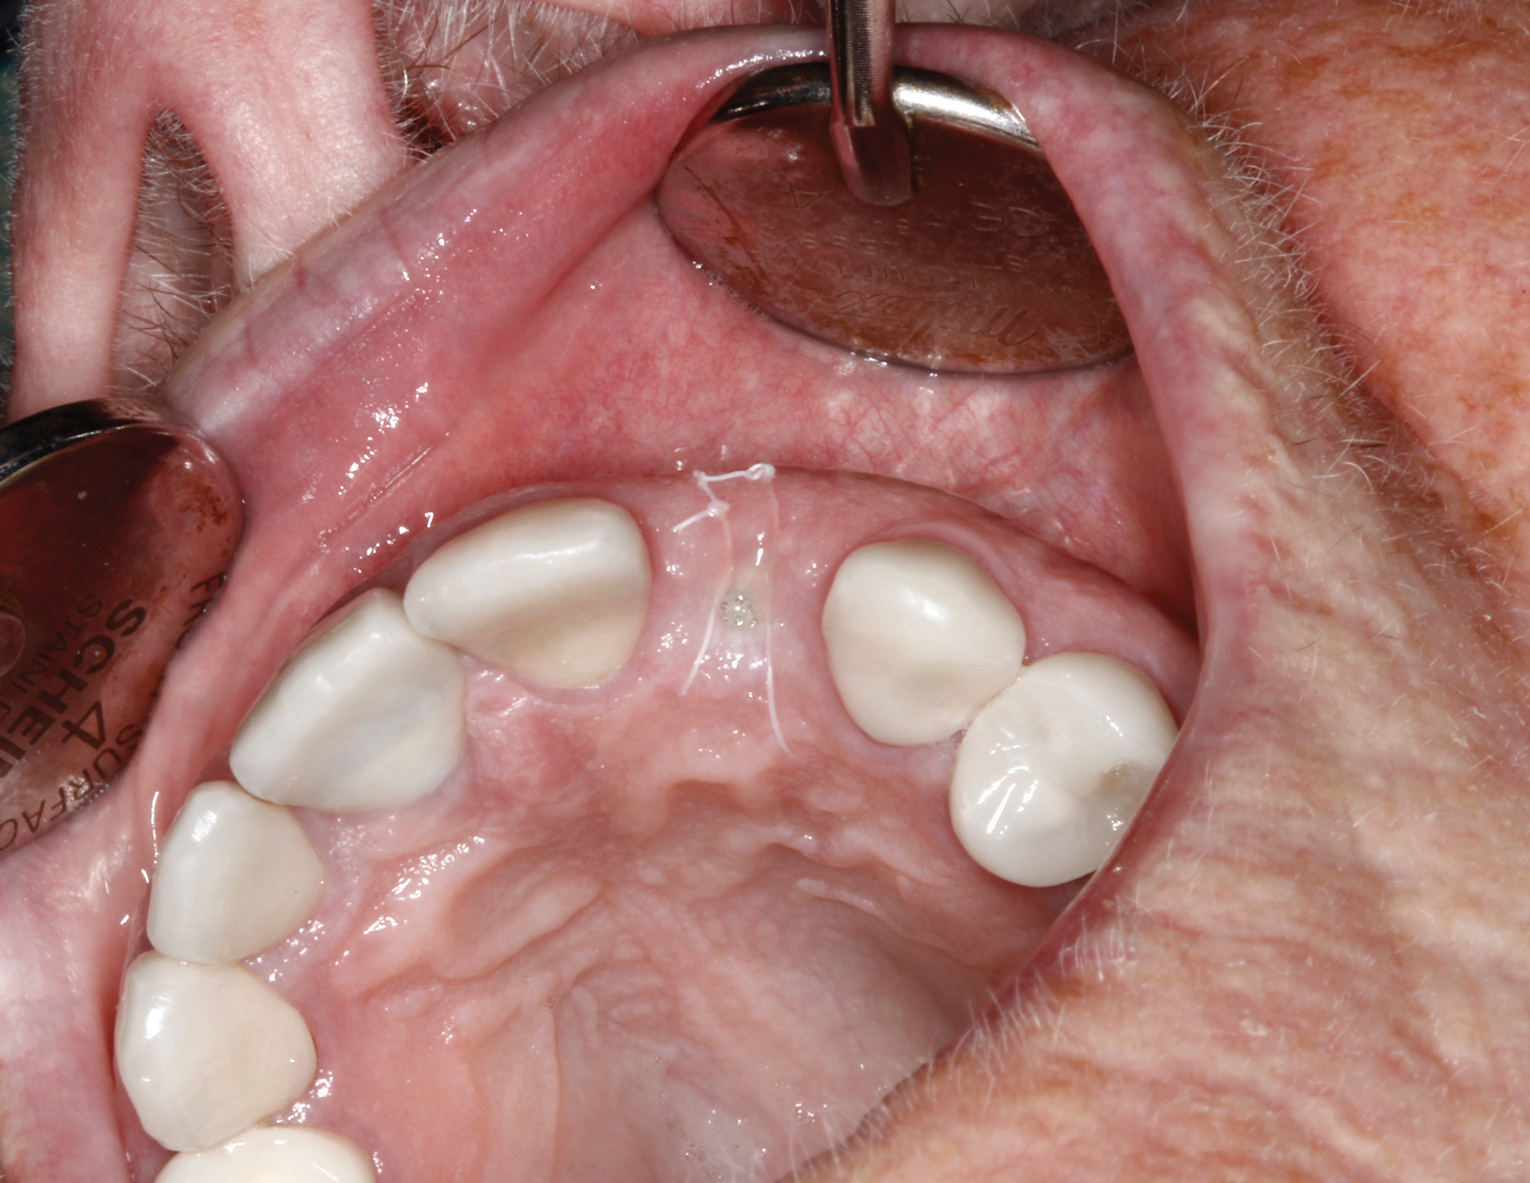

Healing and tissue contours were observed after 10 days (Figure 7) and at subsequent follow-up appointments. Photographs and a radiograph of the restoration at 14 months postoperative demonstrate the successful treatment outcome (Figure 8 through Figure 10).

Fig 8. Restoration at 14 months, occlusal view (Fig 8) and buccal view (Fig 9).

Figure 8

Fig 9. Restoration at 14 months, occlusal view (Fig 8) and buccal view (Fig 9).

Figure 9